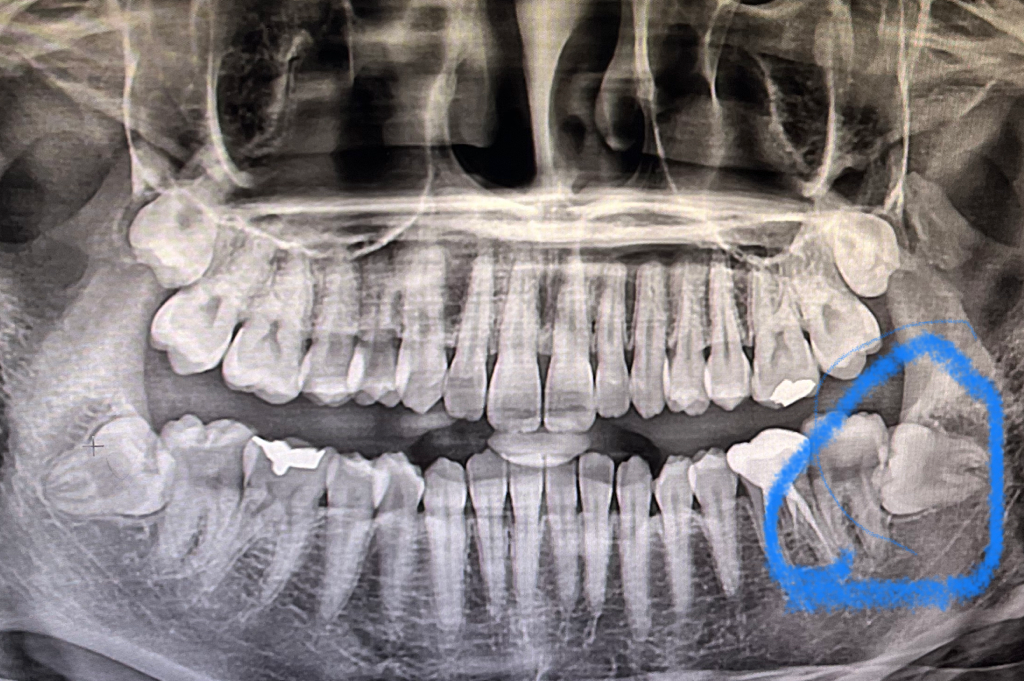

혹시 몰라서 이번에 뽑은 사랑니 표시한 사진이랑 턱찜징팩 사진 첨부합니다!!

• 1번 째 사진